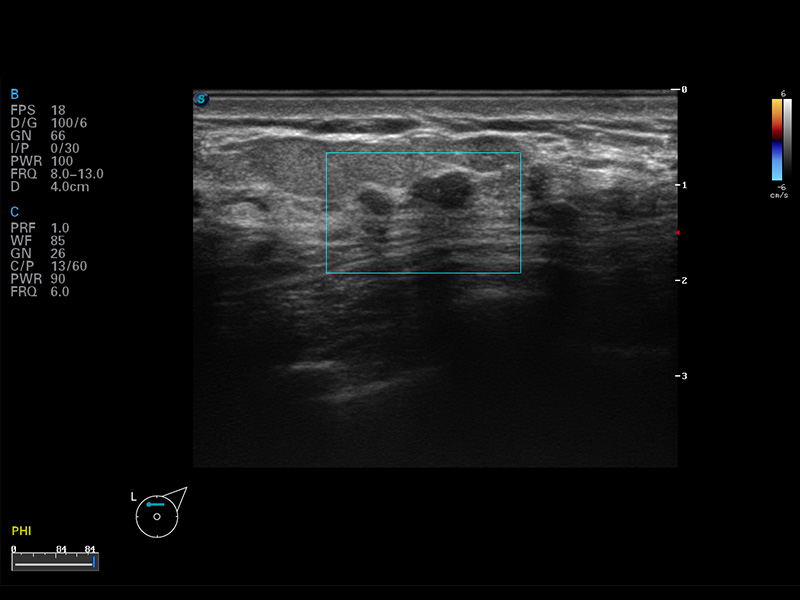

S8 EXP便攜式彩色多普勒超聲診斷儀是開立醫(yī)療研發(fā)的高端全身應(yīng)用型便攜彩超。高通道的VIS平臺融合可視化(Visual)、智能化(Intelligent)和人性化(Smart)的特點,配以開立醫(yī)療自主研發(fā)生產(chǎn)的探頭大家族,使您能夠快速、準確的獲得病人信息,提高工作效率的同時減輕疲勞。

μ-Scan微米成像